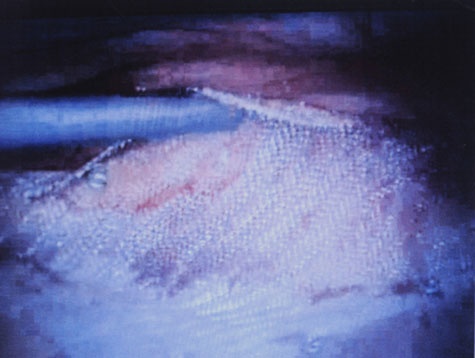

Aplicare plasa cu prolen prin fixare cu agrafe Protack la doi cm decalare.

2008-2-595-6.jpg (26.02 KB)

Fotografie facuta laparoscopic.

2008-2-595-5.jpg (28.72 KB)